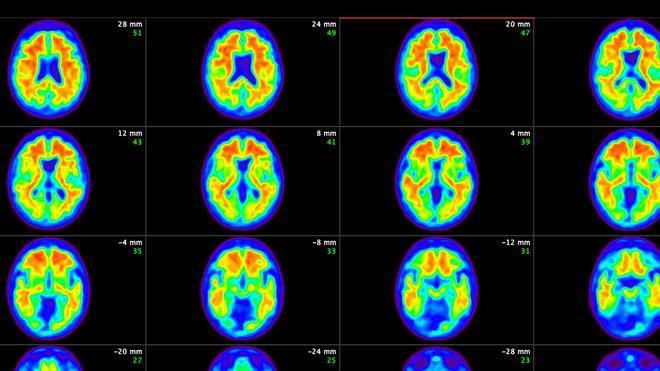

ئەم دەرمانە کار دەکات لەسەر کەمکردنەوەی کەڵەکەبوونی پڕۆتینە نائاساییەکان لە مێشکدا، کە هۆکارێکی سەرەکیی لەدەستدانی یادەوەری و تێکچوونی توانای عەقڵییە. داتا سەرەتاییەکان دەریدەخەن ئەو نەخۆشانەی ئەم دەرمانە وەردەگرن، نیشانەکانیان زۆر خاوتر گەشە دەکات بەراورد بەو کەسانەی چارەسەری ئاسایی وەردەگرن.

پزیشکان جەخت دەکەنەوە کە دەرمانەکە لە قۆناغە هەرە سەرەتاییەکانی نەخۆشییەکەدا زۆرترین کاریگەریی هەیە. ئێستا بەهۆی وێنەگرتنی پێشکەوتووی مێشک و پشکنینی خوێن، کلینیکەکان دەتوانن زووتر ئەو کەسانە دەستنیشان بکەن کە دەتوانن سوود لەم دەرمانە وەربگرن.